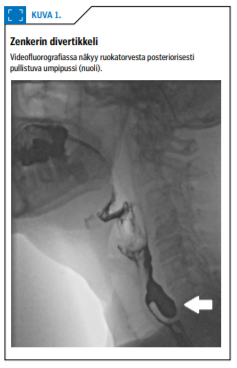

Ruokatorven yläsulkijan alueella keskeisiä rakenteita ovat alin nielunkurojalihas ja rengasrustolihas. Kiinteän ruoan kulku ruokatorveen vaikeutuu, jos rengasrustolihas on hypertrofinen tai se ei relaksoidu normaalisti nielaisun yhteydessä. Lihaksen yläpuolelle voi myös kehittyä posteriorisesti pussimainen laajentuma, Zenkerin divertikkeli (kuva 1 «»2). Nielty ruoka voi kerääntyä siihen ja nousta takaisin nieluun.

Korva-, nenä- ja kurkkutautien erikoisalalla selvitetään nielemisen oraaliseen ja nieluvaiheeseen liittyviä ongelmia. Korvalääkärin vastaanotolla havaitaan suun, nielun ja kurkunpään kasvaimet sekä arvioidaan nielemiseen vaikuttavia sensoriikan ja motoriikan ongelmia. Korvalääkäri voi yhteistyössä puheterapeutin kanssa arvioida nielemistoimintaa tähystyksessä FEES-tutkimuksella (fiberoptic endoscopic evaluation of swallowing), johon yhdistetään potilaan ohjausta (kuva 2 «»5). Alanielun limakalvojen luotettava arviointi edellyttää nukutuksessa tehtävää tutkimusta jäykällä tähystimellä. Korvalääkärille ohjataan potilaat, joilla epäillään rengasrustolihaksen ongelmaa tai Zenkerin divertikkeliä.